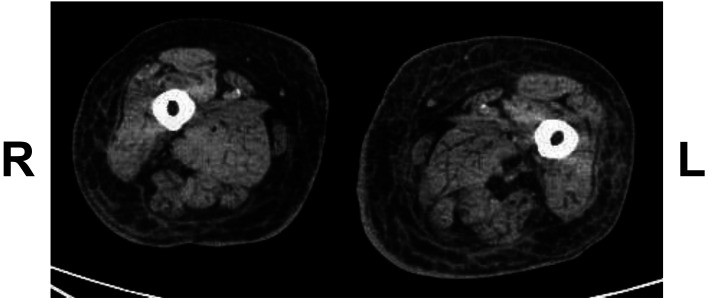

Patient: A Japanese woman in her 80s was hospitalized due to pain in the left leg and difficulty walking. Physical examination revealed diffuse erythema, warmth, swelling, and tenderness in the left thigh and lower leg.

Results: Administration of cefazolin was initiated based on a clinical diagnosis of cellulitis. However, similar erythema appeared on the opposite thigh the following day. Blood cultures obtained on admission yielded L. monocytogenes, prompting a change in antibiotic therapy to meropenem on day 4, followed by ampicillin on day 6. The symptoms in both legs subsequently improved and had nearly resolved by approximately 2 weeks after admission. Antibiotic treatment was continued until day 26. Although the patient died of hepatic dysfunction due to intrahepatic portosystemic venous shunts on day 31, the skin manifestations did not recur during hospitalization.